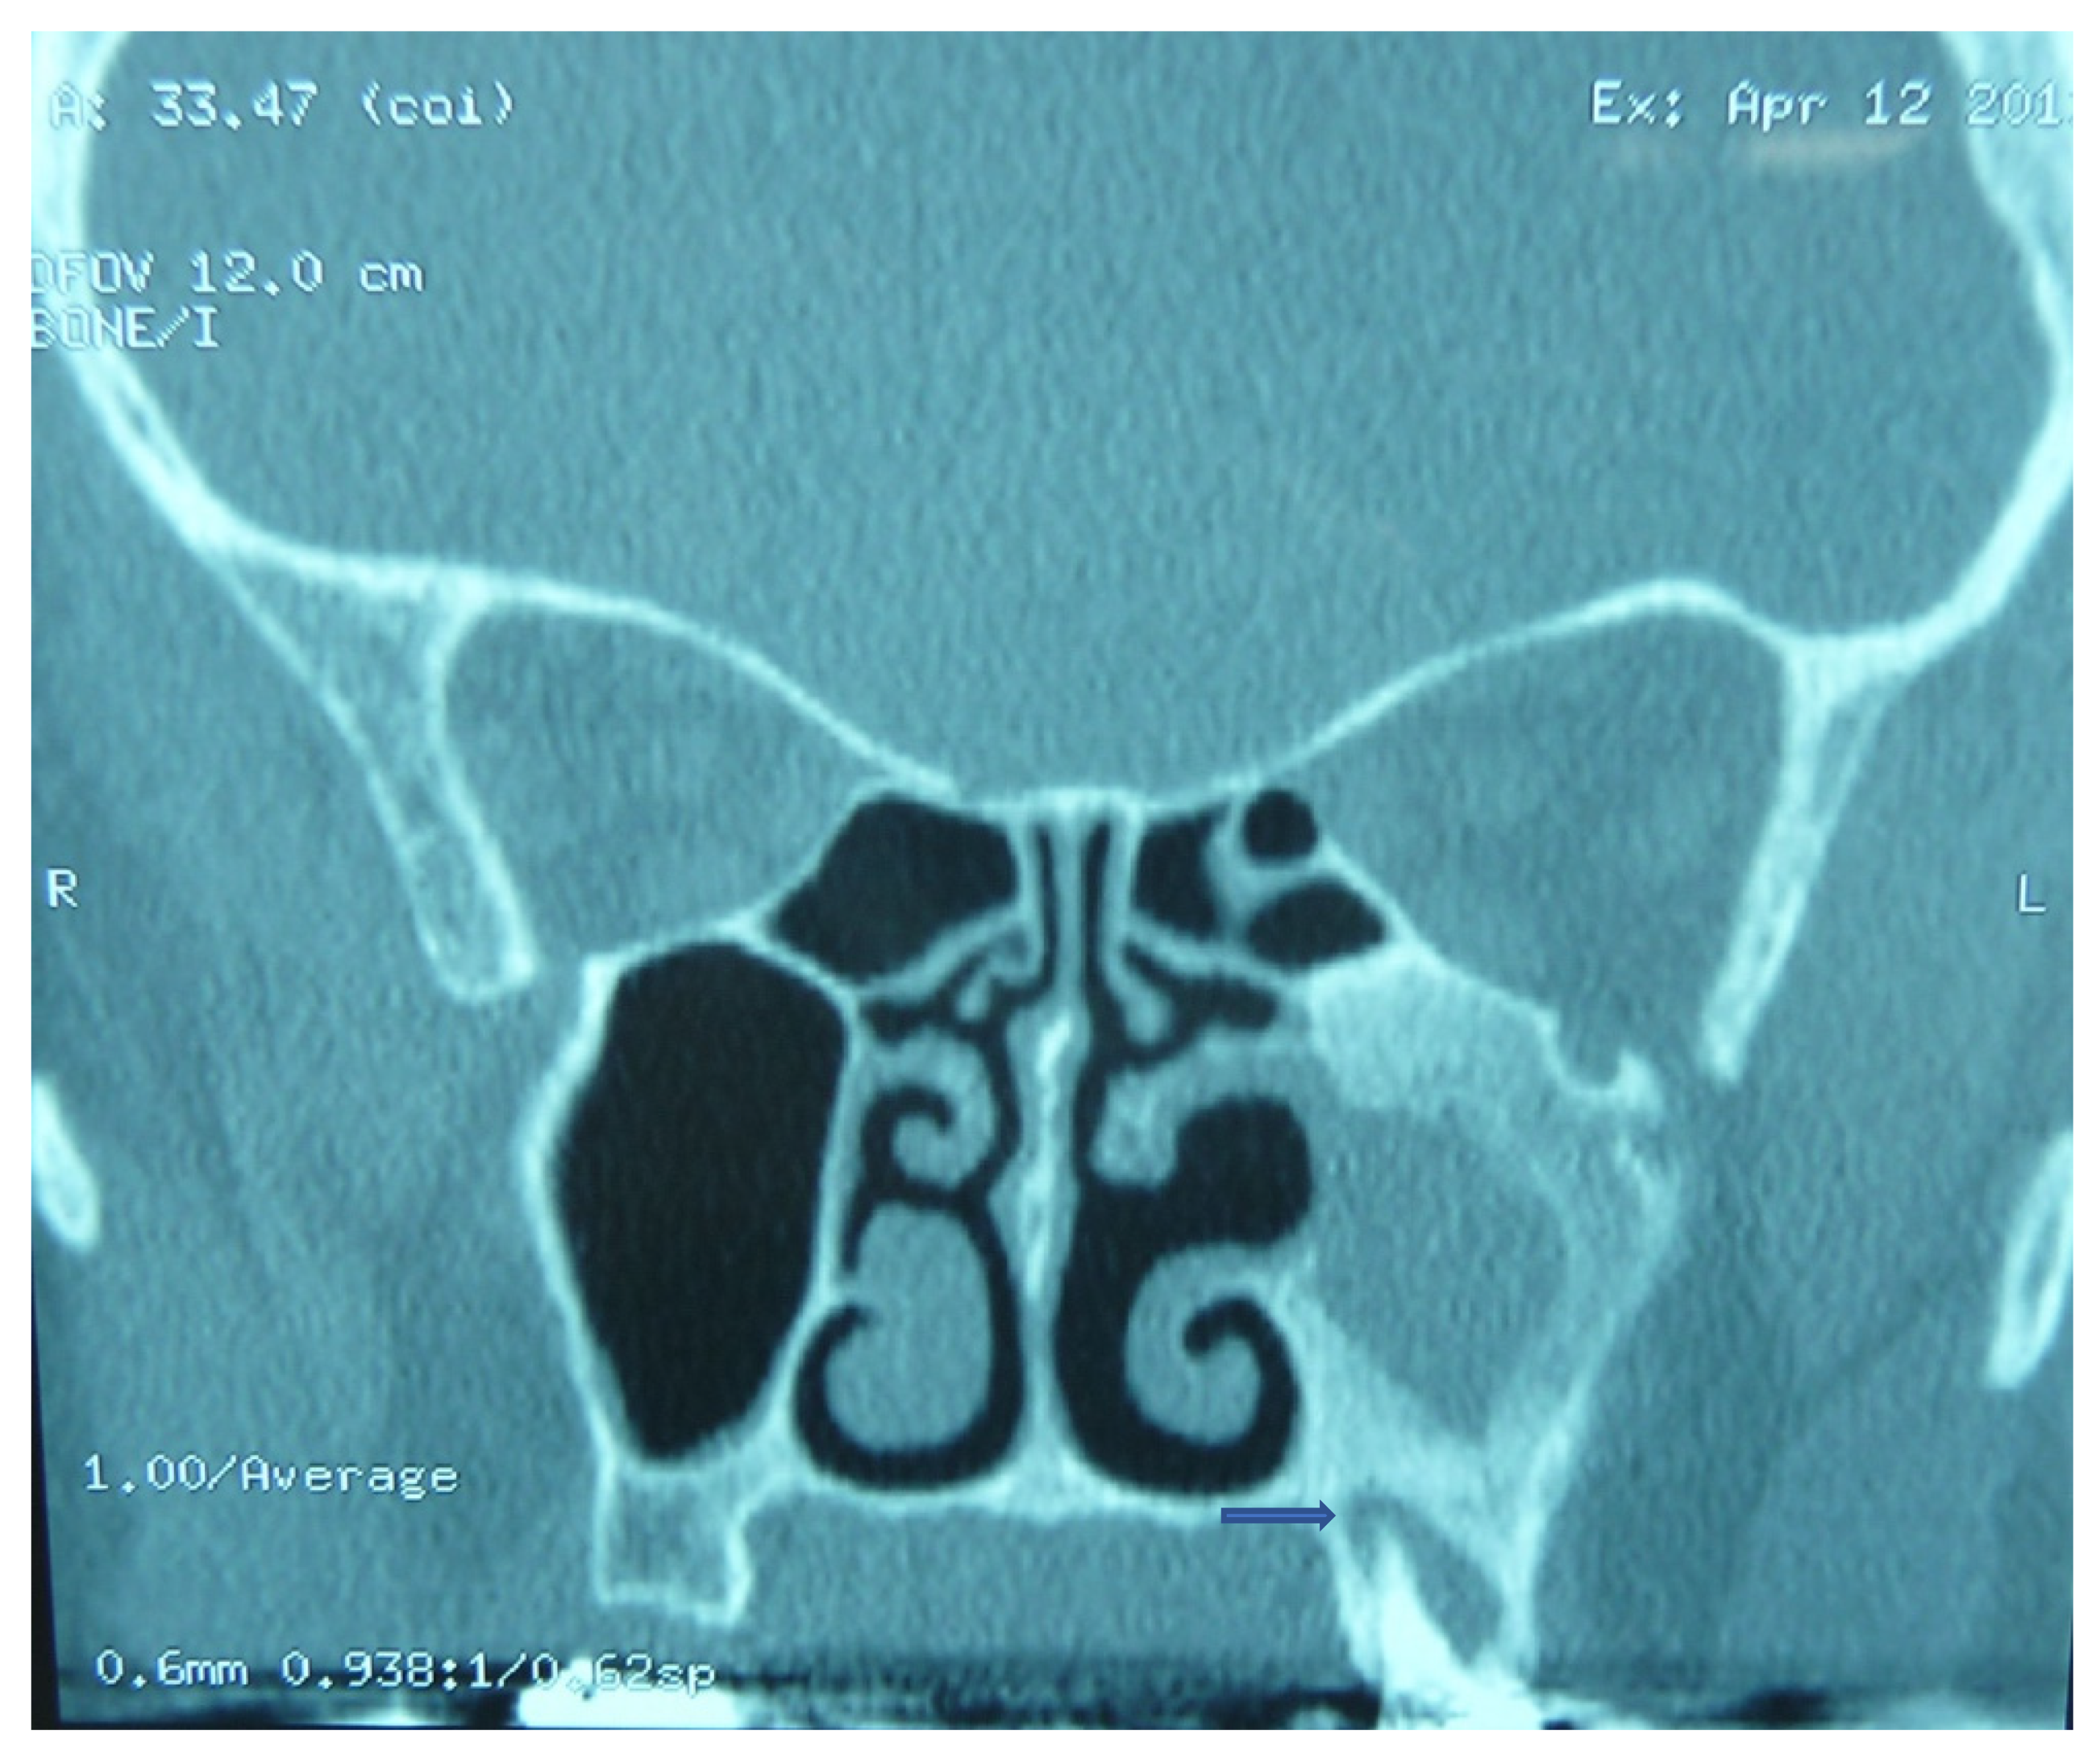

2.1. Iatrogenic